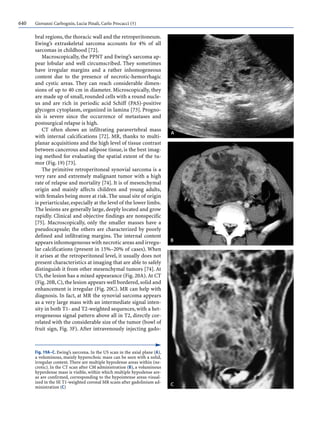

Fig. 2A–D. Densitometric characteristics of retroperitoneal tu-

mors.CT examinations before (A) and after (B–D) CM administra-

tion. A Lipoma. Well-circumscribed lesion with homogeneous fat

density. B Liposarcoma. Voluminous lesion, displacing the intesti-

nal loops toward the left with fat density and within which fibrous

septa are visible. C Leiomyosarcoma. Voluminous lesion originat-

ing from the wall of the vena cava and within which necrotic areas

can be seen. D Ganglioneurofibroma. Solid lesion with clear mar-

gins and low density (myxoid stroma)